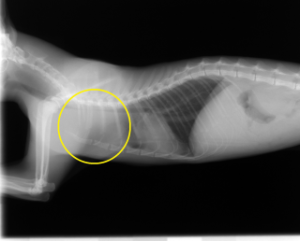

胸腔内(前縦隔)腫瘍

多剤併用療法

治療前 治療後

腫瘍(黄色の丸の部分)がなくなり、圧迫されていた気管も元の位置に戻っています。

腫瘍がレントゲンやエコー検査などで、確認できなくなっている状態(寛解)です。

寛解後も、この状態を維持する為に、必要により、治療を継続します。